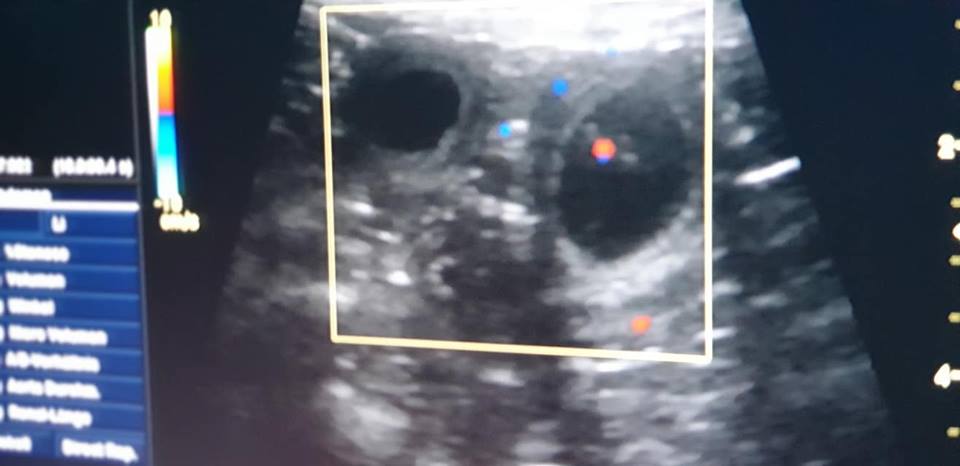

6 Wochen alt - Fotoshooting mit Micha & Maddy4 Wochen alt2 Wochen alt1 Woche altErste Eindrücke 14.04.2019 Thorsten 14.04.2019 ThorstenDie ElternUnsere Berny -mit einem Klick zu Bernies Seite- (Fairy Floss' Dr. Bernadette Maryann Rostenkowski-Wolowitz) & Strolch (Meadow Valley's It Wasn't Me) werden, wenn alles nach Plan verläuft Mitte Februar 2019 Welpen bekommen.Update 2019-01-09: Bernie bekommt Babies! Der Ultraschall hat vitale Anlagen gezeigt. Wir freuen uns!   Wenn ihr Interesse an einem tollen Begleiter habt, freuen wir uns auf euer Kontaktformular... KONTAKT  17.02.2019 Thorsten 17.02.2019 Thorsten